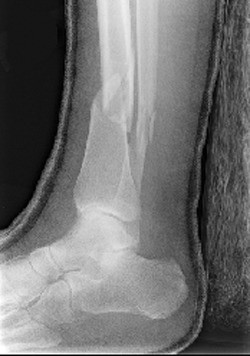

| Look at the radiographs below. Both images show a patient with a fracture of both the tibia and fibula. In this case, the fractures are laterally and anteriorly displaced. | |

Lateral View |